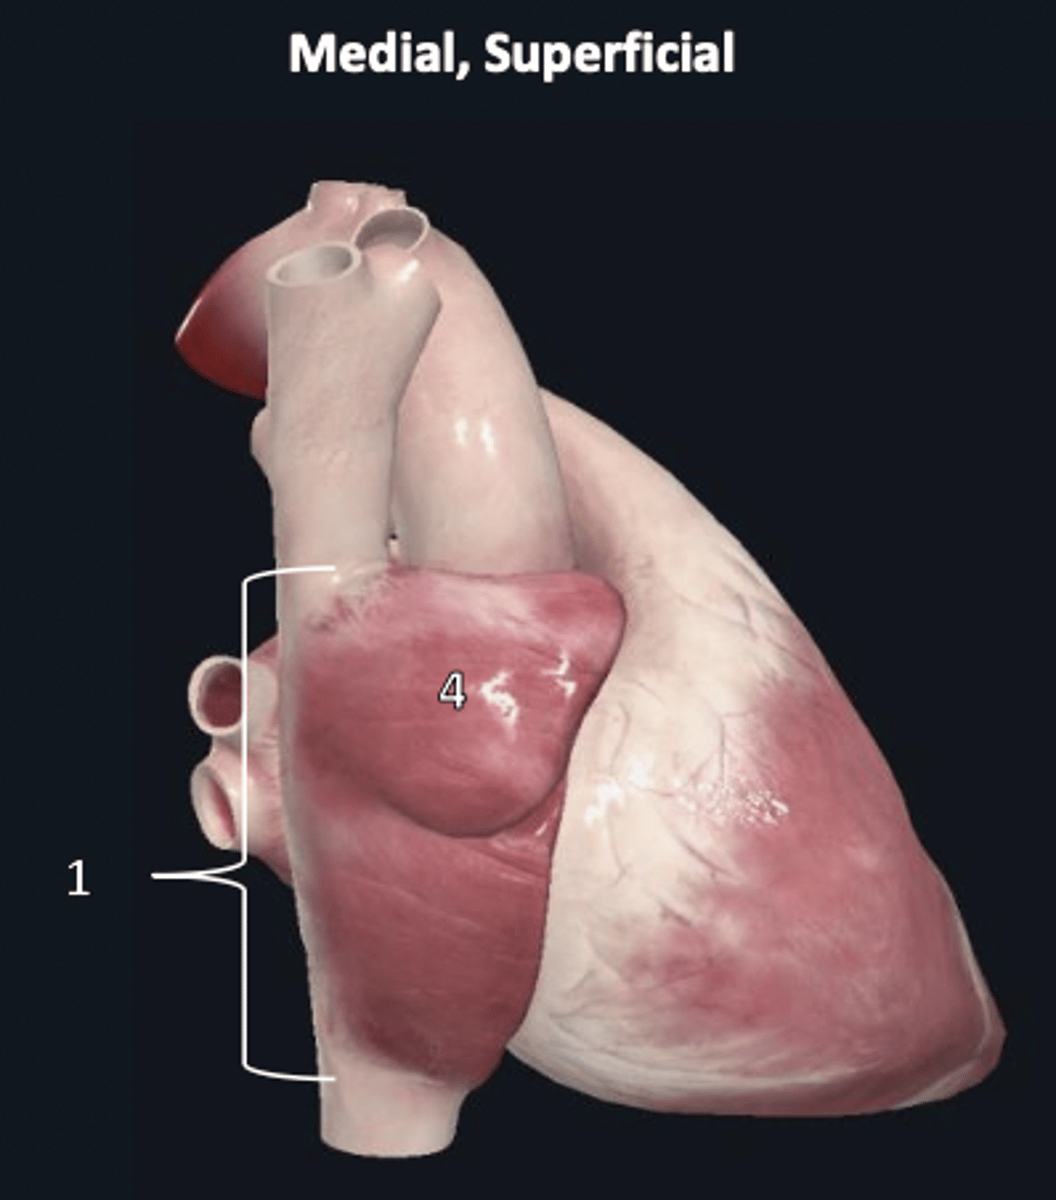

fibrous pericardium

1 (superficial)

right auricle

4